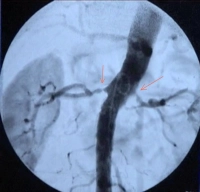

Perioperative management - Percutaneous transluminal angioplasty (PTA) and stenting in bilateral renal artery stenosis - Vascular surgery

• High grade unilateral or bilateral RAS (>70%) with the aim of organ preservation (see indication in video clip)

• RAS in single kidney function